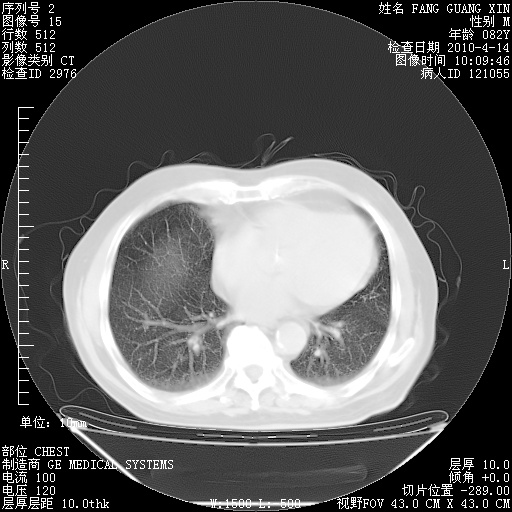

楼主| 发表于 2010-4-28 16:59 | 显示全部楼层

4月28日肺部CT——再次出现类似去年5月9日——透光度降低,(影像科认为)“间质性”改变。

楼主| 发表于 2010-4-28 17:00 | 显示全部楼层

4月28日肺部CT——再次出现类似去年5月9日——透光度降低,“间质性”改变。

楼主| 发表于 2010-4-28 17:02 | 显示全部楼层